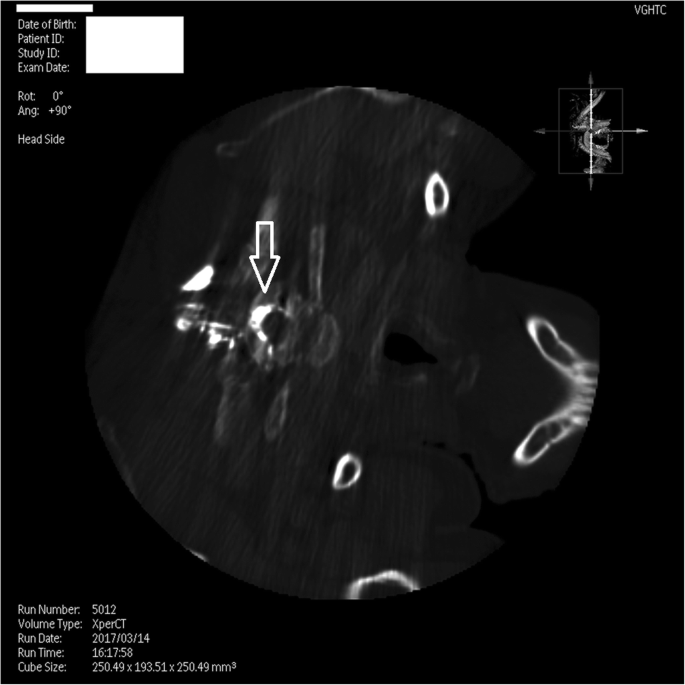

The MR images revealed dural sinus engorgement, contrast enhancement along the neural sleeves of the left C6–7, as well as bilateral C7-T1, T1–2, T2–3, T3–4, T4–5, and T5–6. High signal intensity stripes with a length less than the width of the thecal sac were found, and type C lesions were defined [4]. MR myelography (MRM) depicted the lesions causing CSF leakage along the C-T spines (Fig. 1). Epidural fluid accumulations at the dorsal aspect of the T1–9 spinal canal were observed (Fig. 2). The diagnosis of SIH was made, and EBP treatment was arranged. CT-guided EBP was chosen because a blind technique might have made it difficult to distinguish the epidural space from the intrathecal space. For the EBP injection, the C7-T1 interspinous space was not chosen because the space was not obviously palpable. The approach from the T1–2 interspinous space was tried, but the Tuohy needle was too short to reach the epidural space, so consequently the Tuohy needle was inserted into the T2–3 epidural space assisted by both a fluoroscopy and CT-epidurography (Figs. 3, 4, 5). Autologous blood (18.5 ml) was slowly injected into the T2–3 epidural space. The patient’s headache and dizziness improved greatly after EBP, and he was also able to both stand and walk around without any obvious signs of discomfort. After 16 months of follow-up, the patient’s symptoms had not relapsed.

T2-weighed MR image reveals contrast enhancement along the bilateral neural sleeves of T2-T3. The lesion reveals a high signal intensity stripe with the length less than the width of the thecal sac. According to the typing system proposed by Chen et al. [4], a Type C lesion was defined at T2-T3. Arrow: CSF leak lesions